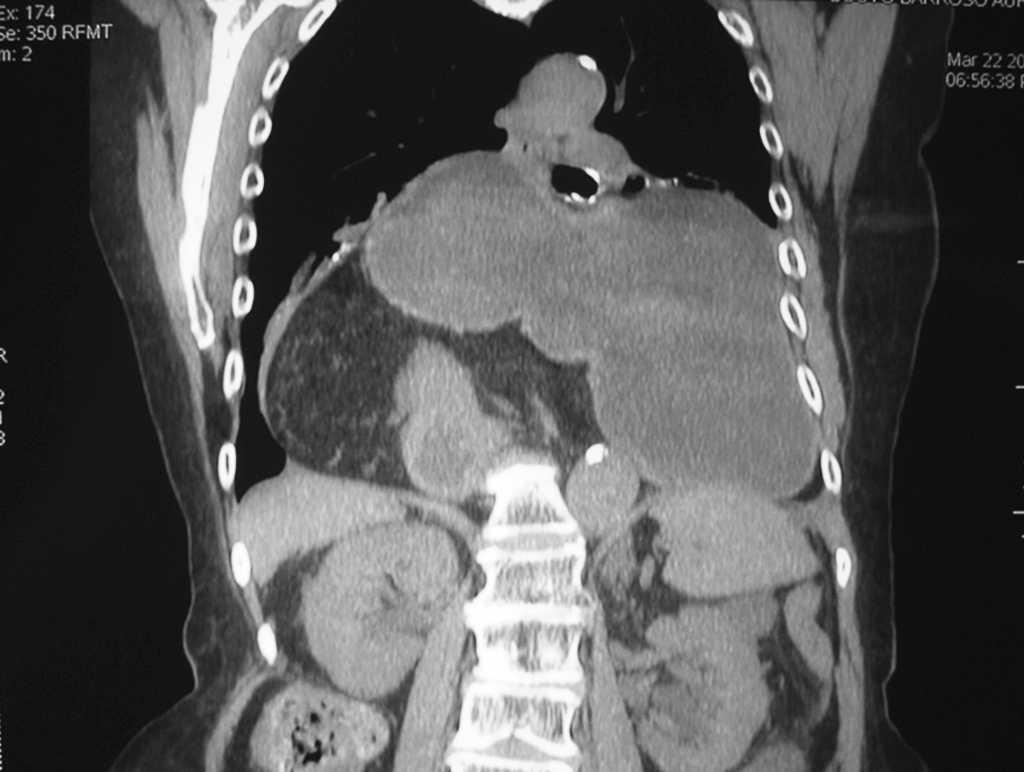

Presentamos el caso de un vólvulo gástrico agudo incarcerado debido a una hernia diafragmática en una anciana de 86 años, con un traumatismo toracoabdominal hace 30 años por accidente de tráfico. La paciente acude a urgencias con importante dolor abdominal de tipo cólico, localizado en el ámbito epigástrico, náuseas sin vómitos e incapacidad para la introducción de una sonda nasogástrica. Como datos analíticos destacan anemia y leucocitosis con desviación izquierda. La tomografía computarizada toracoabdominal realizada de urgencias informa de una gran hernia diafragmática, con ascenso a la cavidad torácica del estómago, duodeno proximal, asas de intestino delgado, ángulo hepático del colon y grasa intraabdominal, con datos de obstrucción y estrangulación. La paciente es intervenida de urgencia mediante laparotomía media supraumbilical; se realiza reducción del saco herniario, sutura de los pilares diafragmáticos y gastrostomía. La evolución es favorable en el postoperatorio.